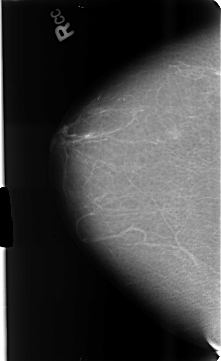

B_3433_1.RIGHT_CC

RIGHT_CC LINES 4688 PIXELS_PER_LINE 2872 BITS_PER_PIXEL 12 RESOLUTION 50 NON_OVERLAY